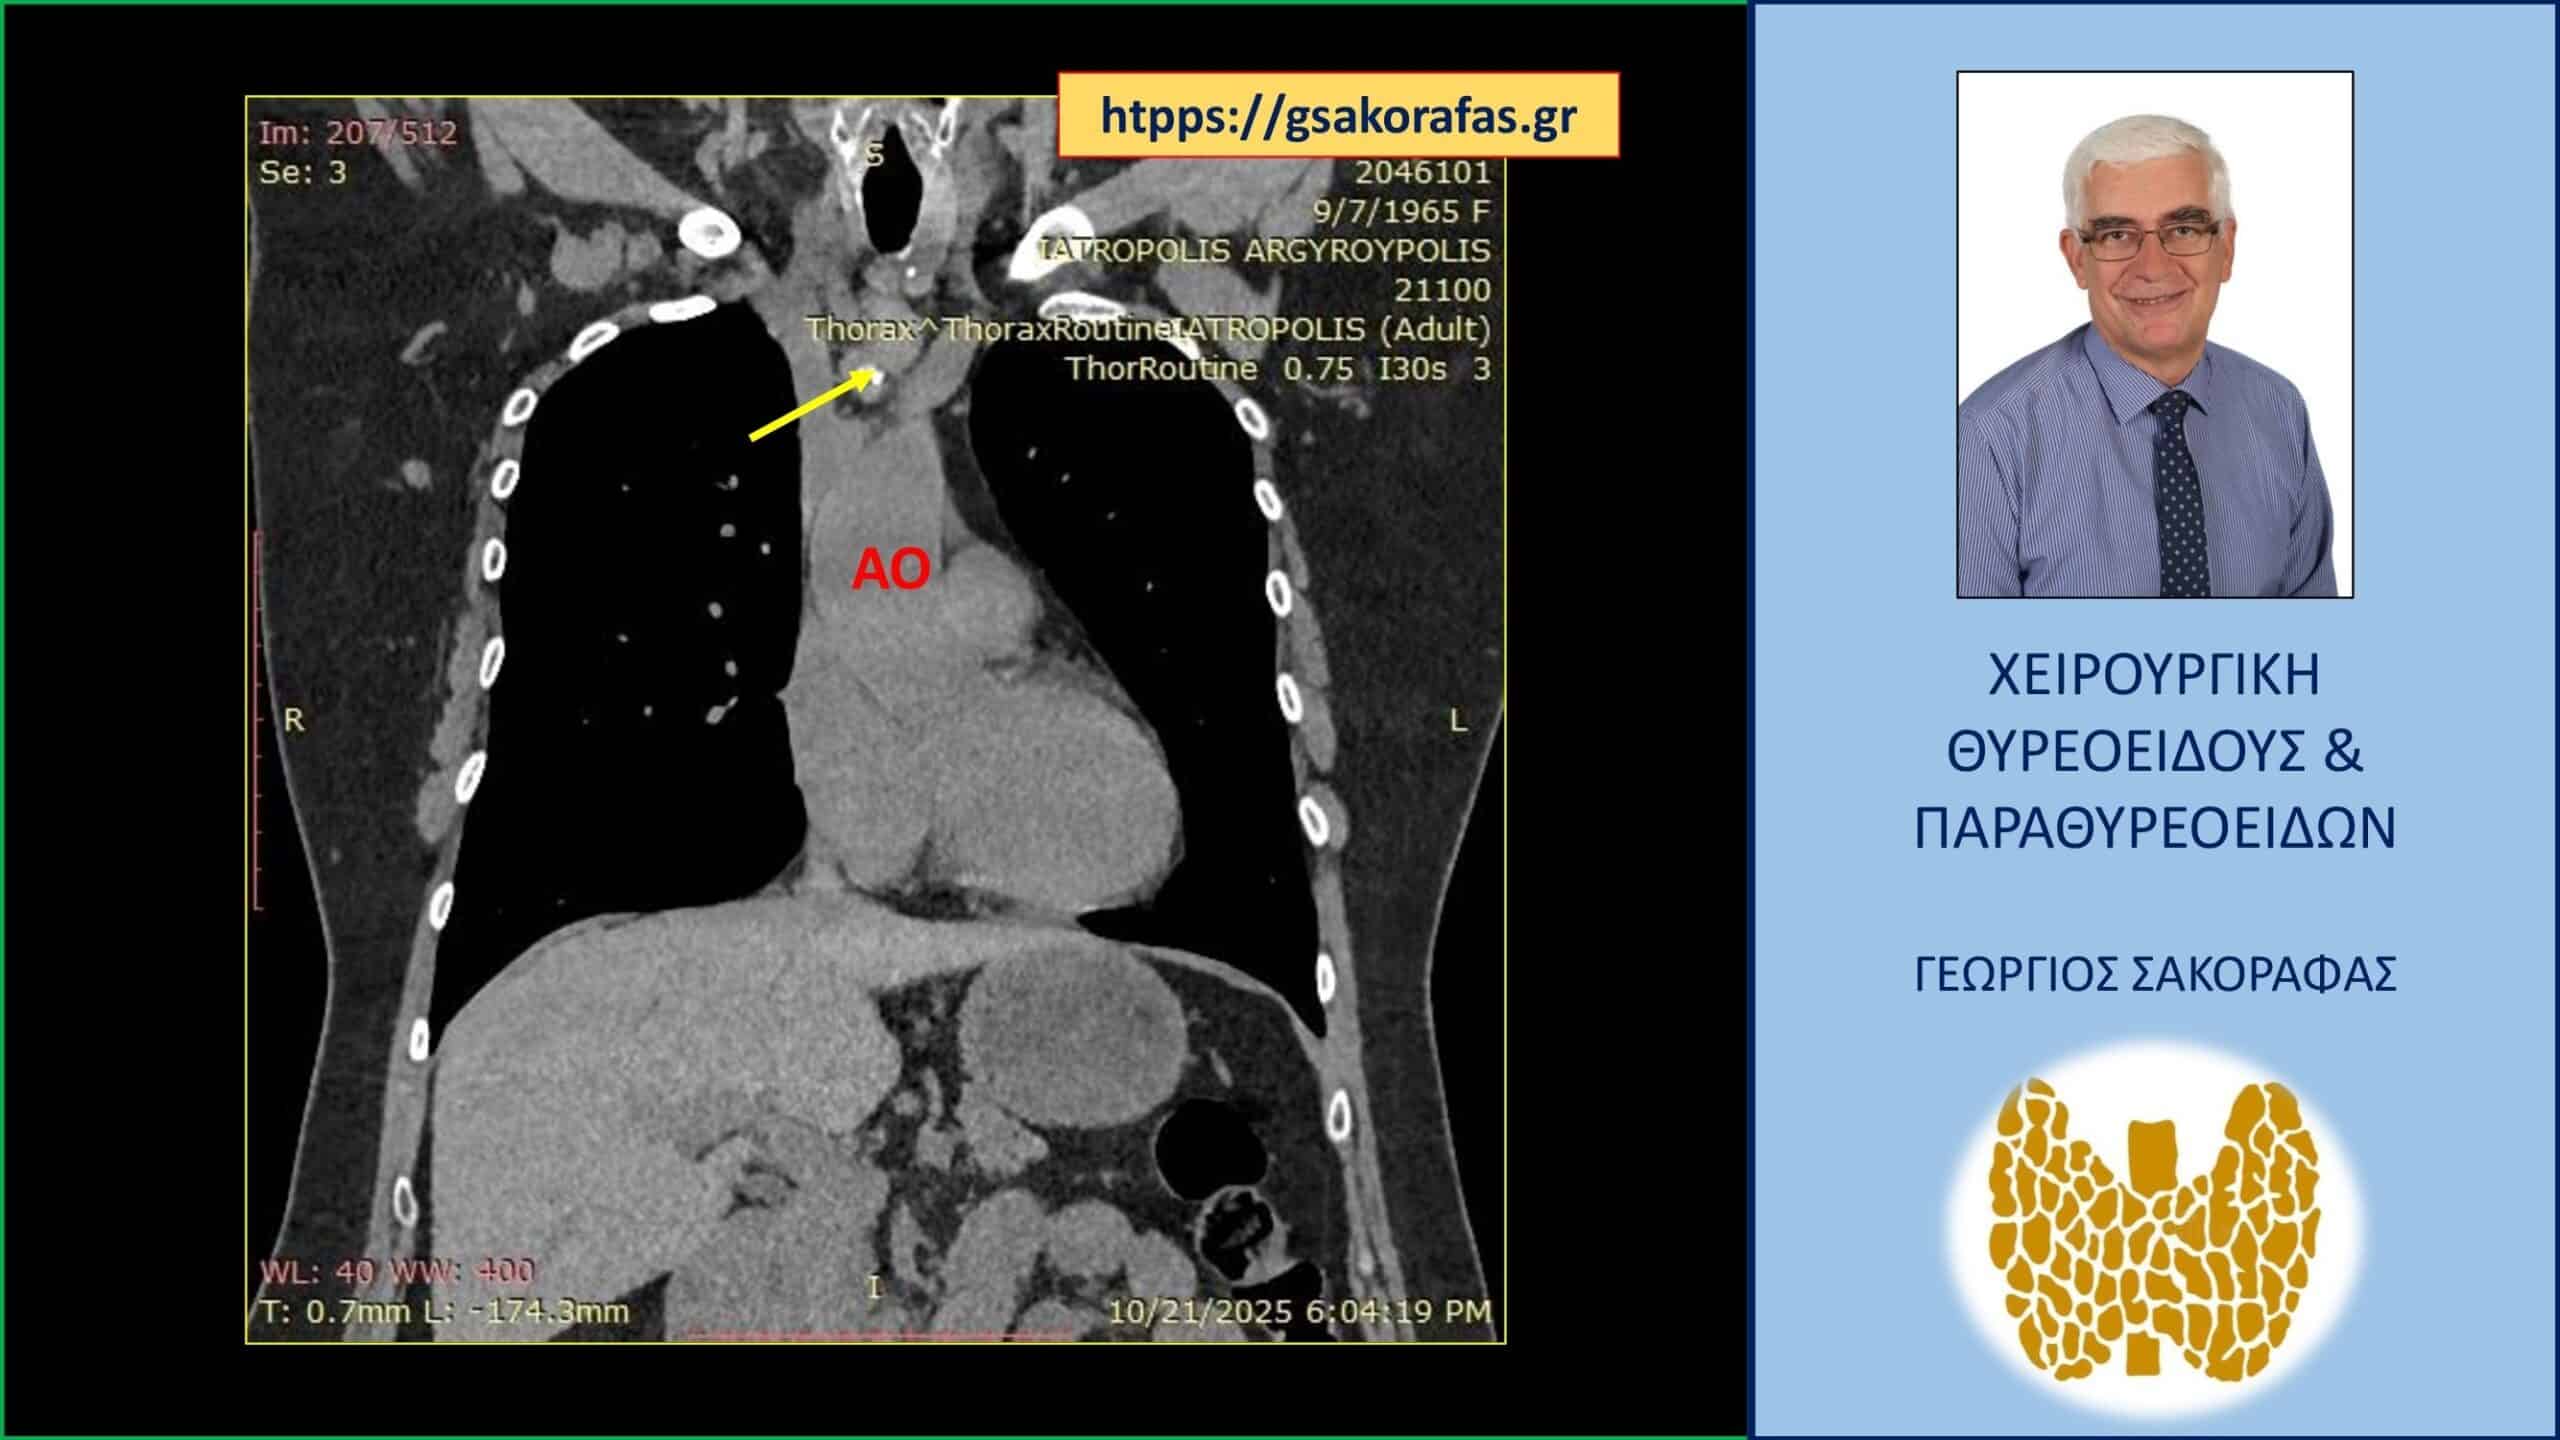

Απεικόνιση στην αξονική τομογραφία (προσθιοπίσθια διατομή). Ο όζος (με αδρή αποτιτάνωση) (κίτρινο βέλος) και η εγγύτητά του στο αορτικό τόξο (ΑΟ)

Αξονική τομογραφία

Στην αξονική τομογραφία που έγινε για την μέτρηση του βαθμού κατάδυσης, ο καταδυόμενος όζος απεικονίσθηκε οπισθοστερνικά στο ανώτερο πρόσθιο μεσοθωράκιο, αμέσως έμπροσθεν και άνωθεν της ανωνύμου αρτηρίας, στην έκφυσή της από το αορτικό τόξο, φθάνοντας στις παρυφές αυτού.